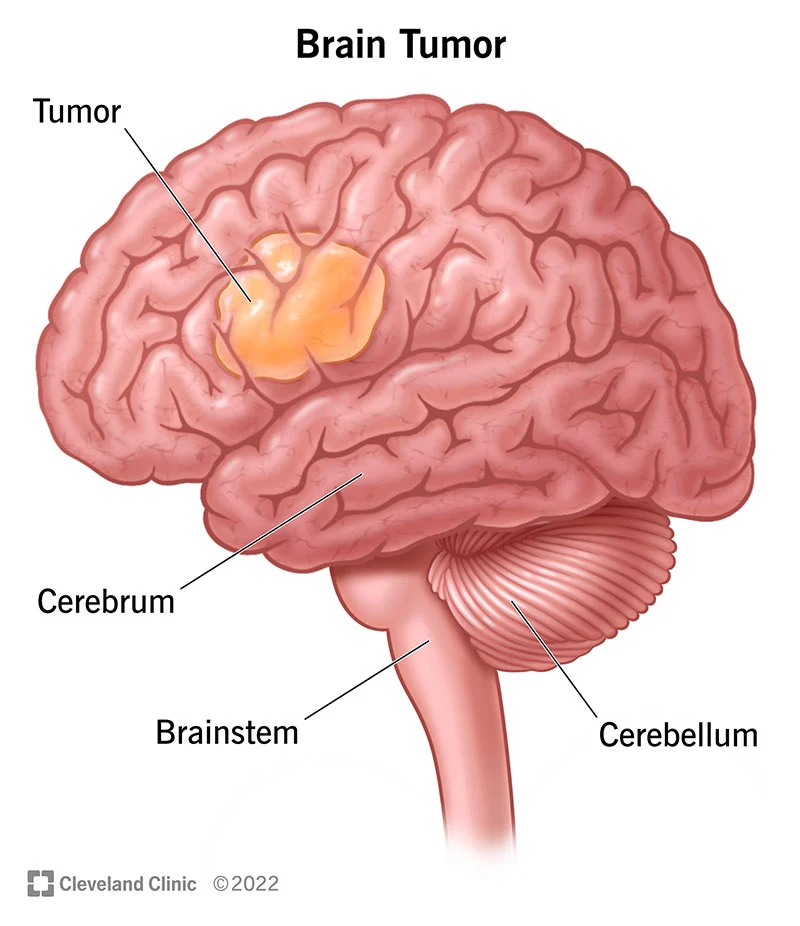

A brain tumor is a collection or mass of abnormal cells in your brain. A brain tumor can be cancerous (malignant) or noncancerous (benign).

A brain tumor is an abnormal growth of cells in the brain. Tumors can be either benign (non-cancerous) or malignant (cancerous). They can originate in the brain (primary tumors) or spread to the brain from other parts of the body (secondary or metastatic tumors).